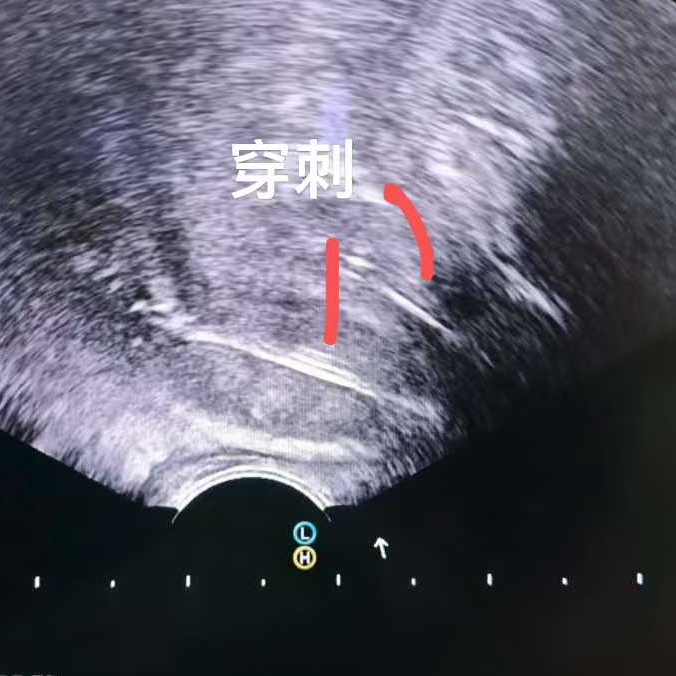

比如这位马来西亚患者,PSA指标正常,但影像却发现可疑病灶,结果穿刺证实是少见的前列腺尿路上皮癌,在我院接受了冷冻消融治疗。